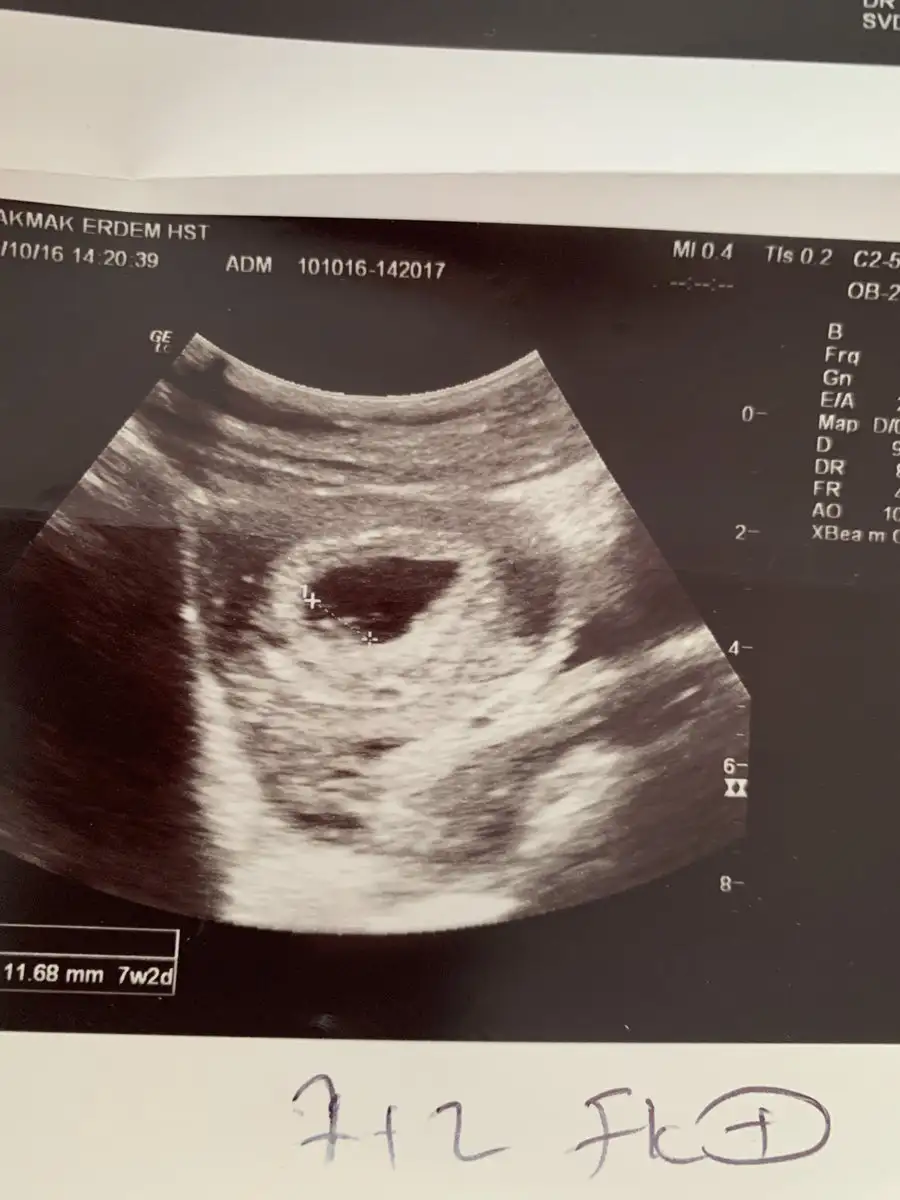

Bak aynı doktor aynı makine bu da kızım 7+2 :) demek istediğim bu

Eklentiler

• image.webp

image.webp

34,6 KB · Görüntüleme: 60